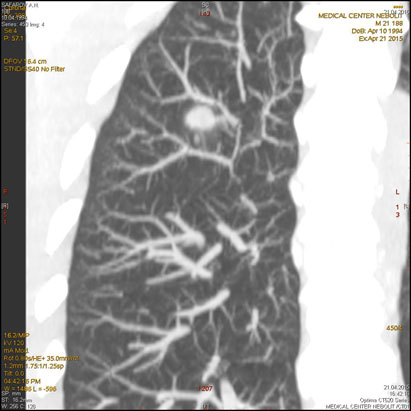

МСКТ органов грудной клетки (легких и средостения).Рентген является базовым методом исследования грудной клетки. МСКТ применяется в выявлении стадии рака легкого, туберкулеза, определяет структуру патологических образований, таких как киста, солидный компонент, сосудистые, жидкостные и воздушные полости, подозрение на ТЭЛА.

С появлением МСКТ уходит в прошлое КТ с высоким разрешением для диагностики интерстициальных заболеваний легких. При использовании МСКТ можно дифференцировать диффузные интерстициальные процессы в легких альвеолит, бронхиолит, саркоидоз, канцироматоз и очаговые изменения.

Астма и хронический бронхит диагностируются клинически. Половина больных с хроническим бронхитом имеют нормальную картину при рентгенографии. При МСКТ у пациентов можно выявить признаки обструкции-участки вздутия легочной ткани обусловленные закупоркой мелких бронхов, участки гиповентиляции за счет отека слизистой, эмфизематозные буллы, дисковидные ателектазы, бронхоэктазы.

- для уточнения наличия очагов отсева или полостей распада при специфических поражениях легких и средостения

Эмболии лкгочной артерии, источником которых обычно являются тромбы в венах таза и нижних конечностей являются грозным и относительно частым осложнением особенно у лежачих больных и после операции. Данные при рентгенографии неспецифичны. Без инфаркта может определяться приподнятие купола диафрагмы и сужение теней сосудов к периферии. Возможности МСКТ в диагностике ТЭЛА в ряде случаев позволяют отказаться от проведения инвазивной ангиографии.